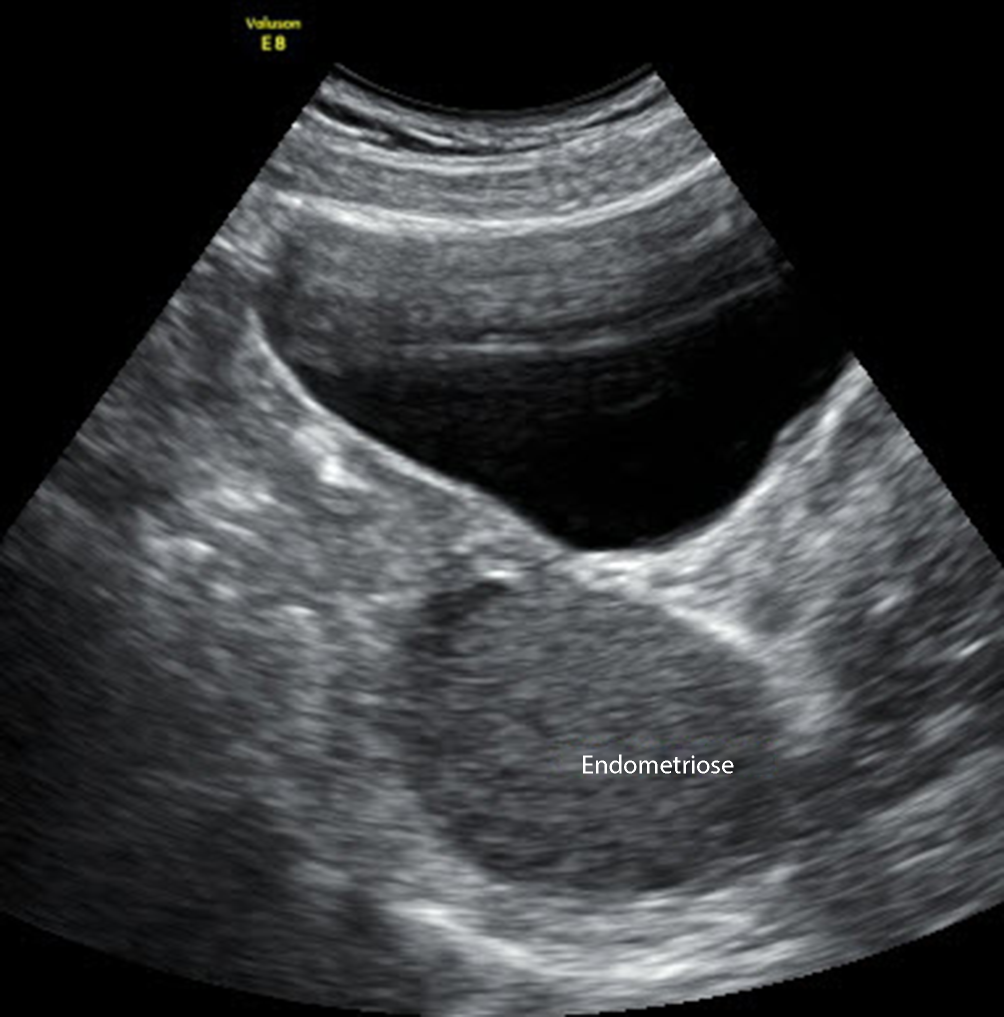

Abb. 11

Unilokuläre Zyste nach IOTA von abdominal geschallt mit 3‑D-Funktion